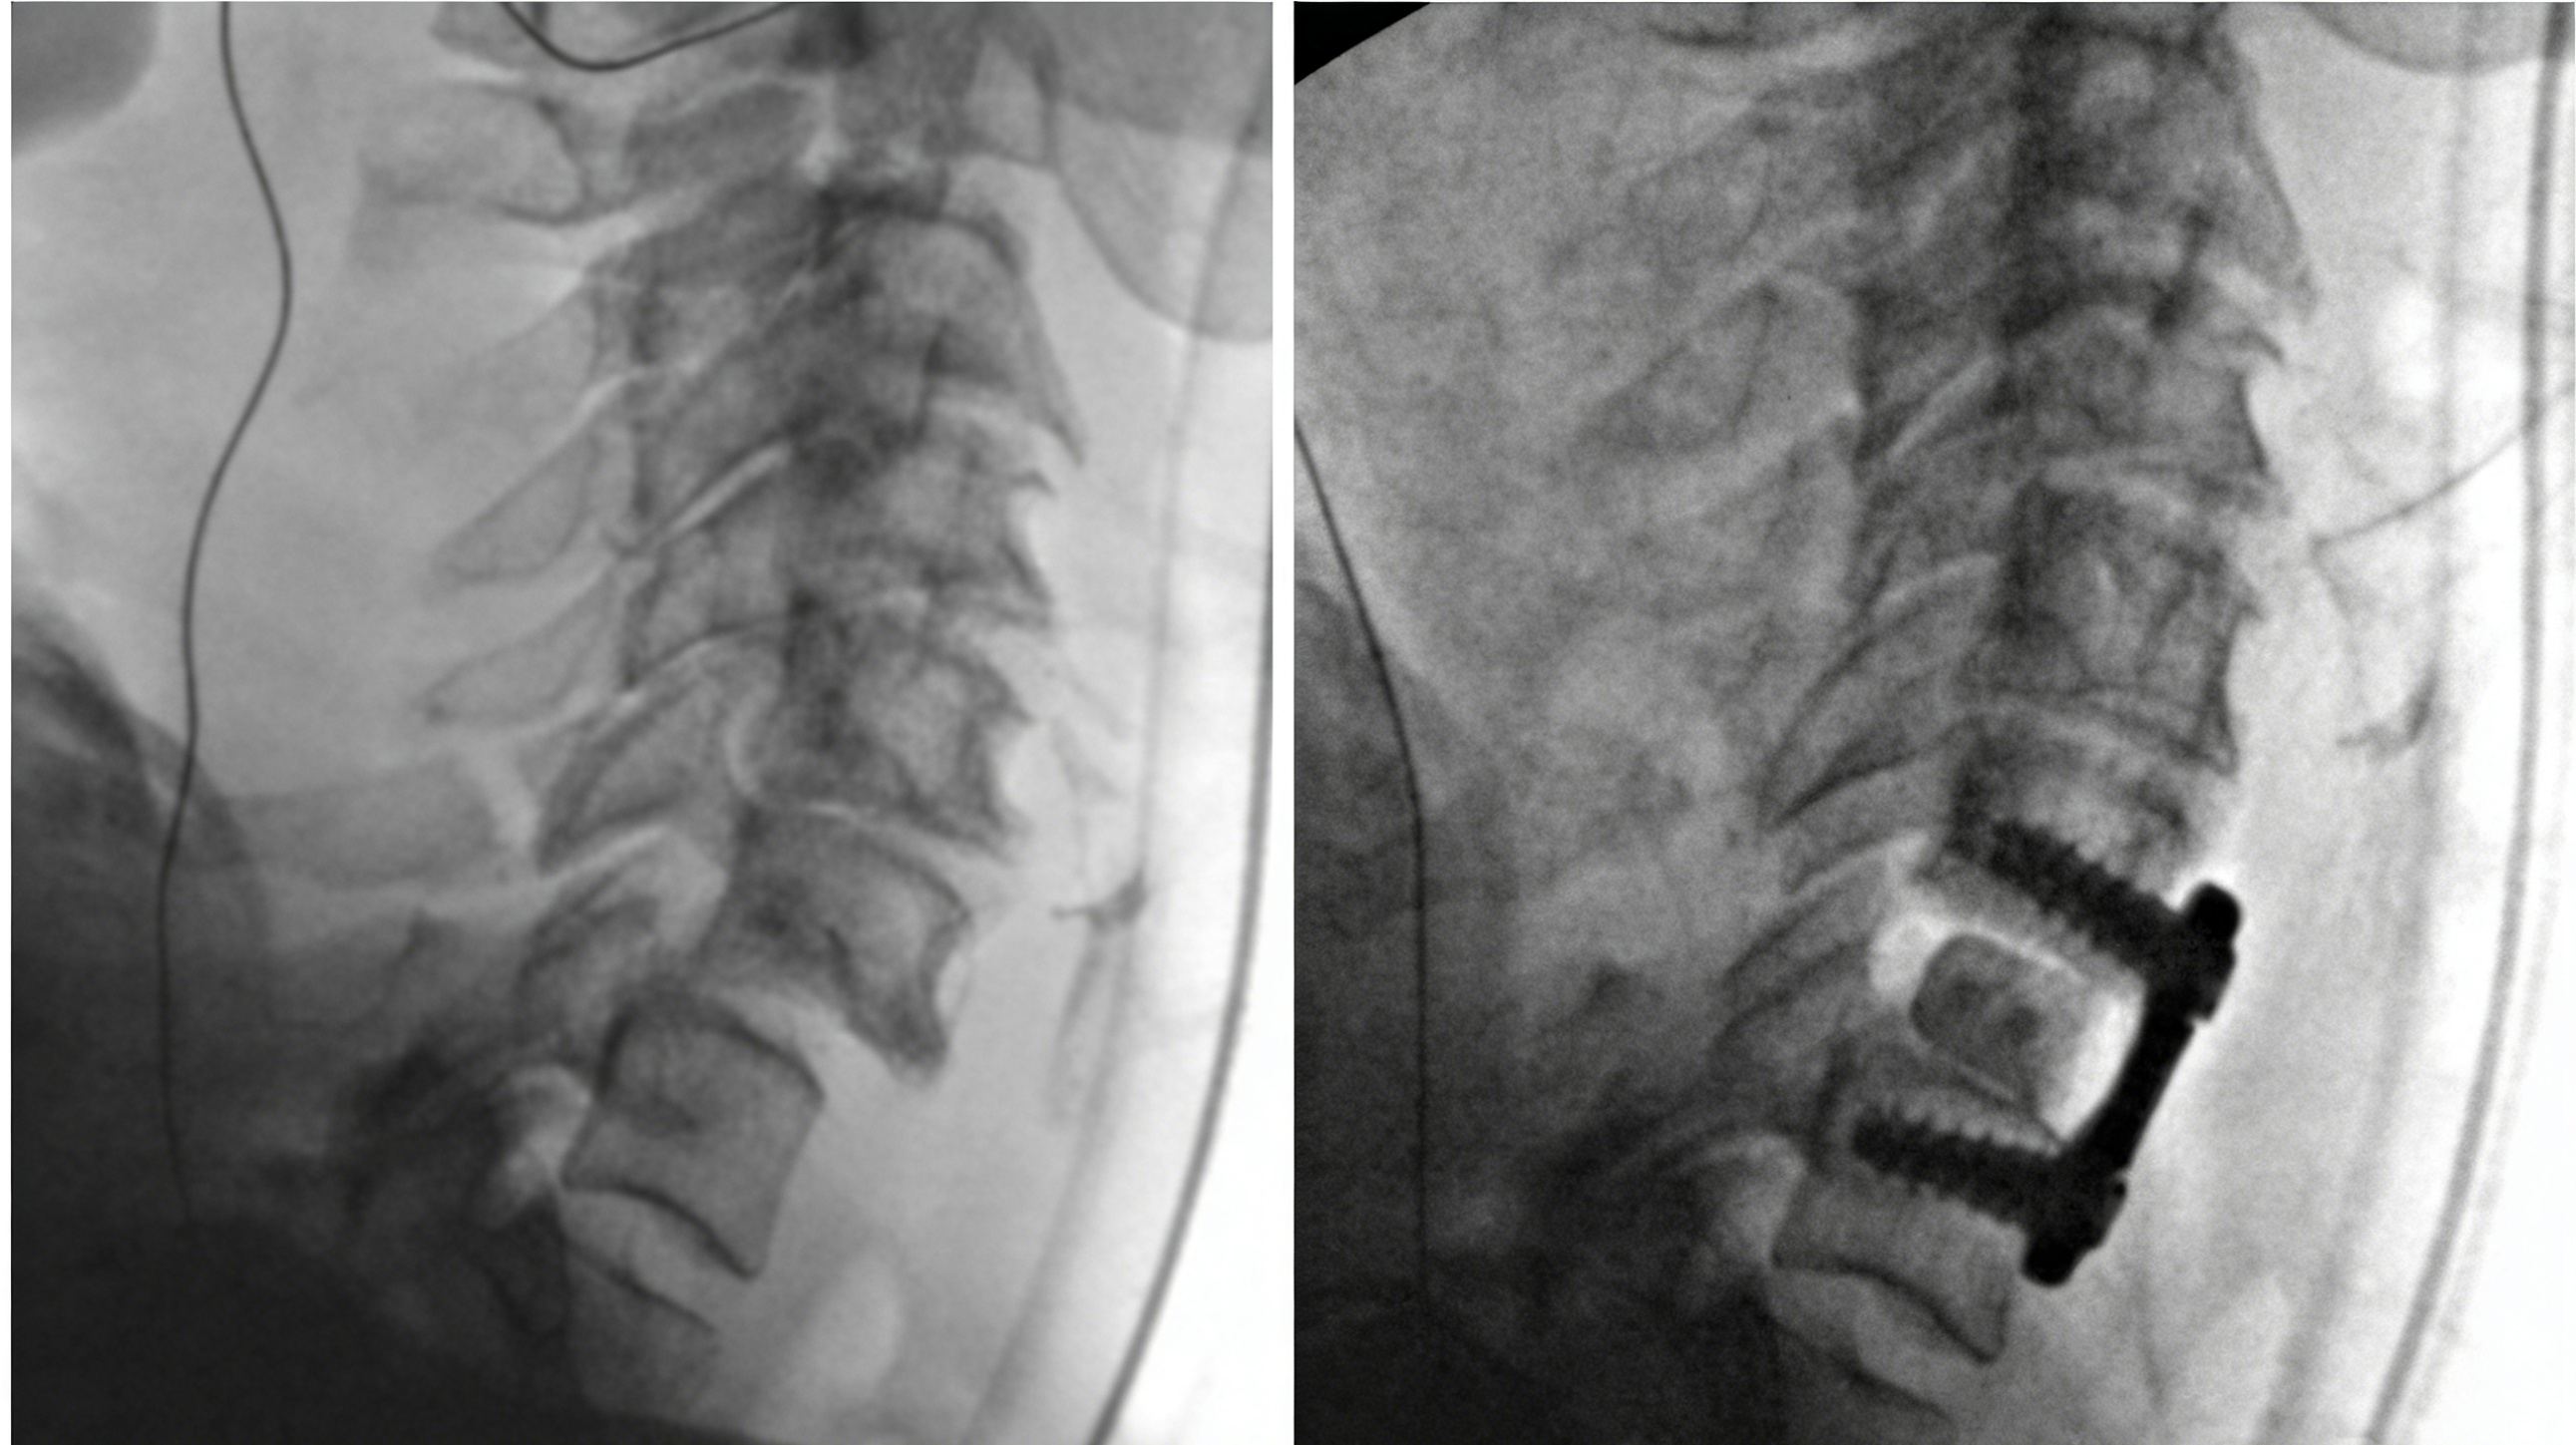

4_副本.jpg

CT and MRI following acute symptom recurrence after ACDF, showing failure of C6-7 ACDF and reduction of bilateral locked facets. A: Mid-sagittal CT showing C7 screw pullout, C6-7 dislocation, and a vertical fracture of the C7 vertebral body with displacement of the synthetic cage. B: Left parasagittal CT demonstrating locked facets. C: Right parasagittal CT also showing locked facets. D: Mid-sagittal T2-weighted MRI revealing abnormal spinal cord signal intensity at C7. E: Mid-sagittal STIR sequence showing signal through the C7 vertebral body. F: Axial view through the C6-7 disc space demonstrating severe stenosis and spinal cord compression.